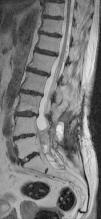

The patient underwent magnetic resonance imaging (MRI) of the low back, which revealed an intradural space-occupying lesion in the conus medullaris. It was hypervascularized and receiving its supply of blood from a rosary-like vessel,4 that extended from T10, occupying nearly the entire spinal canal to the level of L5. Spinal angiography confirmed the presence of a hypervascularized tumor irrigated by a medium-sized artery and a large, tortuous anterior spinal artery that was not amenable to embolization5,6 (Figs. 1–3).

The patient remained asymptomatic until the fourth year of follow-up, when she experienced a recurrence, with lumbosciatic pain in her right leg, and lumbosacral MRI revealed tumor progression. Because of the neurological risk of further surgery, the decision was made to embolize the lesion via right pedicle of L4, which resulted in its marked devascularization. After the procedure, the patient remained asymptomatic until the clinical signs reappeared 3 months later. Magnetic resonance imaging showed that the lesion continued to progress, and the decision was made to reoperate. This procedure achieved very limited resection due to adherence of the tumor and scar tissue to the L5 and S1 nerve roots, making it necessary to interrupt the intervention due to the risk of significant neurological sequelae.

To date, she continues to undergo clinical monitoring every 6 months and annual radiological evaluation, and is asymptomatic and the lesion has not grown (Figs. 4 and 5).